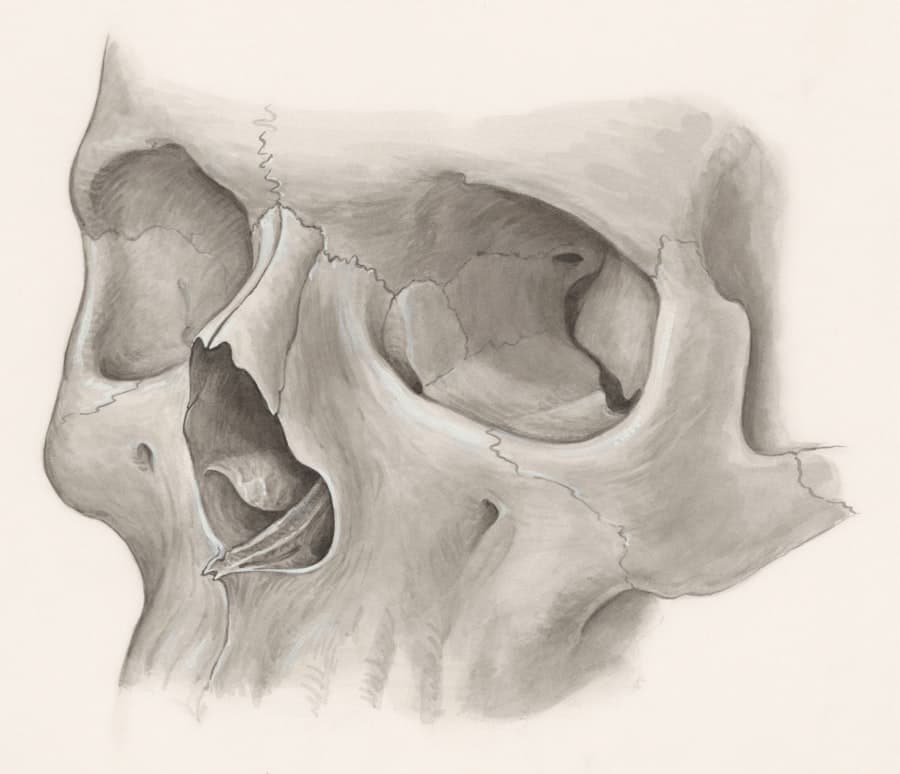

- Physical Examination: A thorough examination of your nose, both externally and internally, is conducted. The surgeon will assess the skin, cartilage, bone structure, and the integrity of the nasal airways. They will look for signs of previous scarring, asymmetry, or structural weakness.

- Open vs. Closed Rhinoplasty: While closed rhinoplasty can sometimes be an option, revision cases often benefit from the enhanced visualization and precision offered by the open approach. This involves a small incision in the columella (the strip of tissue between the nostrils), allowing the surgeon to lift the skin and have direct access to the underlying nasal structures.

- Cartilage Grafting Techniques: In revision rhinoplasty, it’s common to require cartilage grafts to rebuild or provide support to weakened areas. The source of this cartilage can vary.

- Septal Cartilage: If there is sufficient remaining septal cartilage from the first surgery, it can be used. However, this is less common in revisions, as the septum is often involved in the initial procedure.

- Ear Cartilage (Conchal Cartilage): Cartilage harvested from the ear is a frequently used and readily available donor site. It’s malleable and can be shaped to suit various needs.

- Rib Cartilage (Costal Cartilage): For more significant structural support, particularly in cases of severe collapse or when a large amount of cartilage is needed, rib cartilage is often the preferred choice. Harvesting rib cartilage is a more involved process, requiring a separate incision on the chest.

- Preserving Existing Structures: A key aspect of revision rhinoplasty is the preservation of as much healthy native cartilage and bone as possible. The surgeon will carefully assess what can be retained and what needs to be modified or augmented.

- Addressing Airway Obstruction: If functional issues are present, the surgeon will incorporate techniques to improve airflow. This might involve widening the nasal passages, reinforcing the nasal valves (internal or external), or correcting a deviated septum that may have been exacerbated by the first surgery.